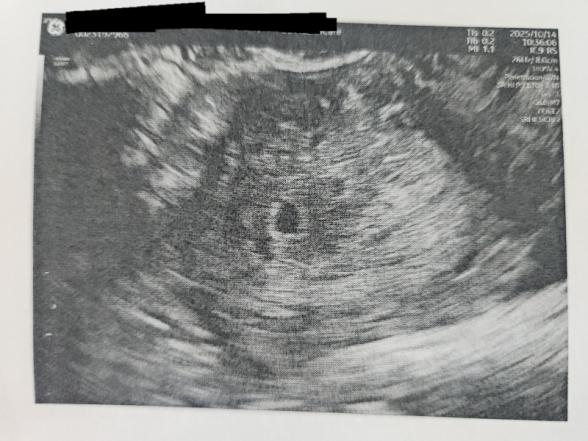

最終月経から6w0dの14日に初受診し胎嚢の確認はできました。

ただ、

赤ちゃんの姿見えないね、4~5wくらいの大きさ、小さめやね、との こと。

胎嚢が5日前の初診からあまり変わってない。

今日の大きさが6.1mmだそうです。

現段階では、胎芽も卵黄囊も見えず